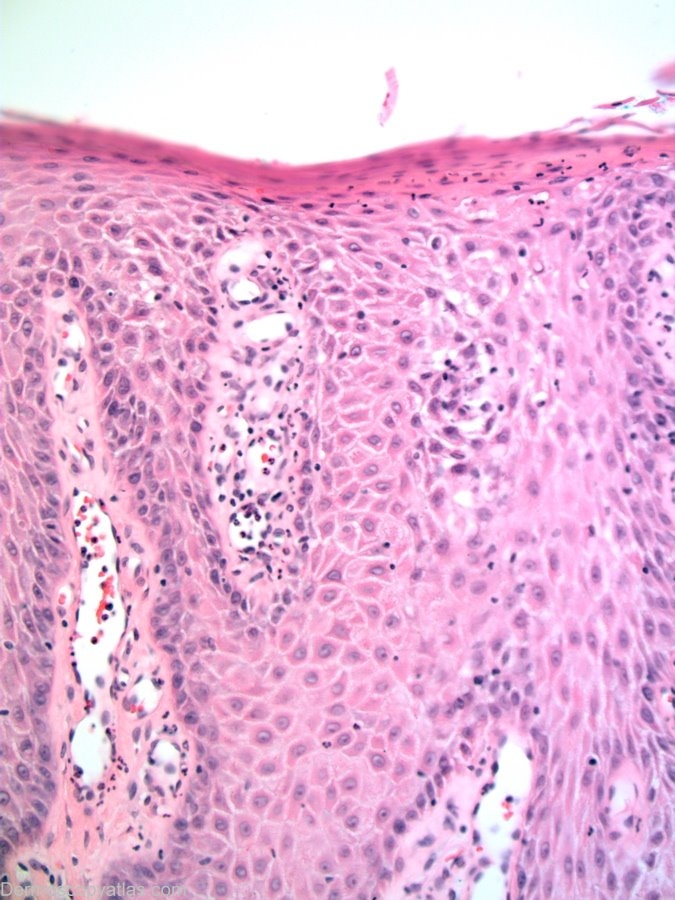

Image Number #2141 (Clear cell acanthoma)

Diagnosis: Clear cell acanthoma

Description: Lesion on the chest wall. Note the string of pearls vessels and the glycogen rich keratinocytes giving the lesion its histological clear colour.

History: Images courtesy of Dr Alan Cameron This lesion arose slowly over a 16 week period. There was no bleeding.